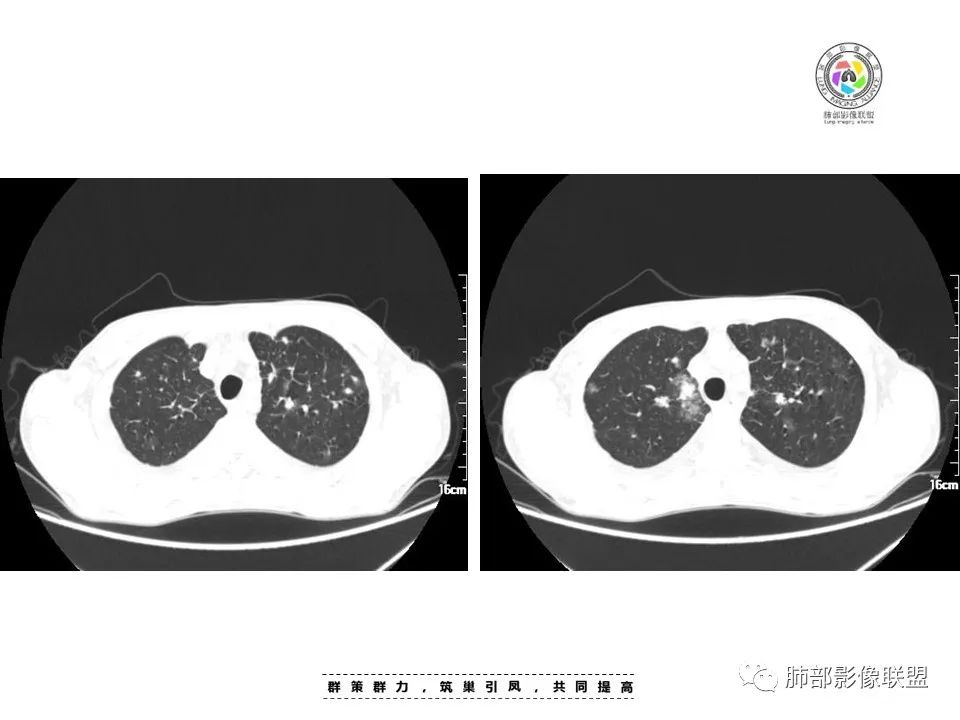

周一晚读病例:男性45岁,发热、纳差,全身散在暗紫色皮疹,结合CD4,符合HIV;肺部影像表现:两肺散在实性结节及磨玻璃密度影,实性结节伴晕征,部分沿支气管血管束分布,支气管血管束增粗,以两肺下叶为著,类似火焰征,双侧胸腔少量积液;首先考虑卡波西肉瘤,鉴别淋巴瘤增值性病变,淋巴瘤样肉芽肿/淋巴瘤,最后挂上马尔尼菲青霉菌病。

两肺弥漫性性结节状、小片状及片状带晕的病灶,煎蛋征、点晕征,主要分布两肺中下叶,病灶周围小叶间隔增厚呈网格状影,部分病灶累及胸膜,伴两侧胸膜增厚。

2.本例双肺小叶间隔增厚明显,多发结节影及片状实性密度影,沿血管支气管束分布为主,两侧较为对称,病灶多环以磨玻璃晕,边界不清。

双侧胸腔少量积液。双肺门及纵隔未见明确肿大淋巴结,纵隔结构间隙模糊。

1.结节型:两肺沿支气管血管束分布的结节影,呈火焰状或星芒状、挂果征,局部周围出血磨玻璃影(肺泡出血或水肿)。

2.支气管血管束增粗型:

肺门周围支气管壁呈“套袖样”改变。